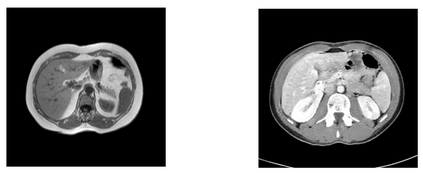

In many clinical settings, the use of both Computed Tomography (CT) and Magnetic Resonance (MRI) is necessary to pursue a thorough understanding of the patient's anatomy and to plan a suitable therapeutical strategy; this is often the case in MRI-based radiotherapy, where CT is always necessary to prepare the dose delivery, as it provides the essential information about the radiation absorption properties of the tissues. Sometimes, MRI is preferred to contour the target volumes. However, this approach is often not the most efficient, as it is more expensive, time-consuming and, most importantly, stressful for the patients. To overcome this issue, in this work, we analyse the capabilities of different configurations of Deep Learning models to generate synthetic CT scans from MRI, leveraging the power of Generative Adversarial Networks (GANs) and, in particular, the CycleGAN architecture, capable of working in an unsupervised manner and without paired images, which were not available. Several CycleGAN models were trained unsupervised to generate CT scans from different MRI modalities with and without contrast agents. To overcome the problem of not having a ground truth, distribution-based metrics were used to assess the model's performance quantitatively, together with a qualitative evaluation where physicians were asked to differentiate between real and synthetic images to understand how realistic the generated images were. The results show how, depending on the input modalities, the models can have very different performances; however, models with the best quantitative results, according to the distribution-based metrics used, can generate very difficult images to distinguish from the real ones, even for physicians, demonstrating the approach's potential.